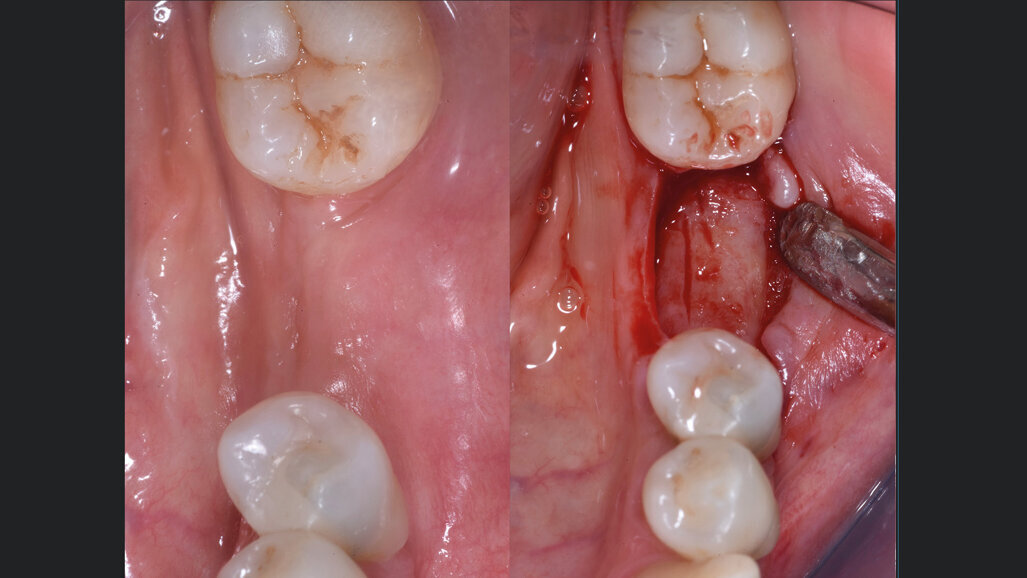

Il giorno prima dell’intervento, la paziente veniva sottoposta a terapia antibiotica con Amoxicillina e Acido Clavulanico compresse da 1 gr ogni 12 ore. Il giorno dell’intervento veniva eseguita la profilassi antibiotica 1 ora prima dell’inizio con 1 g di Amoxicillina più Acido Clavulanico e veniva praticata l’anestesia locale con Articaina più adrenalina 1:200.000. All’apertura del lembo veniva confermata clinicamente l’atrofia orizzontale a livello dell’elemento 36 (Fig. 2). Il sito veniva opportunamente gestito. L’innesto veniva preparato inizialmente miscelando i granuli cortico-spongiosi a collagene preservato con il gel osteopromozionale in rapporto 1:1, andando a formare un conglomerato adesivo che facilita la successiva apposizione. Tale procedura permette, al contempo, di idratare l’innesto e di aumentarne il potenziale rigenerativo, in virtù della presenza di matrice ossea demineralizzata. Parallelamente, la lamina corticale flessibile veniva idratata per 10 secondi in soluzione salina tiepida (Figg. 3, 4). Infine, l’innesto eterologo veniva caricato sulla lamina corticale flessibile pre-idratata con la tecnica del “taco” e quindi inserita a colmare l’atrofia orizzontale (Fig. 4). I lembi venivano chiusi con delle suture in PTFE 4.0 per favorire la guarigione per prima intenzione (Fig. 4). A 6 mesi dalla GBR, l’aspetto clinico mostrava un’ottima guarigione dei tessuti molli e un notevole incremento orizzontale della cresta alveolare. All’apertura si evidenziava la risoluzione dell’atrofia orizzontale e l’innesto eterologo completamente sostituito da osso neoformato e sanguinante alla sua perforazione (Fig. 5).

Fig. 5 - A sinistra, l’aspetto ottimale dei tessuti molli a 6 mesi dalla GBR. A destra, la riapertura che mostra la risoluzione dell’atrofia orizzontale e il rimodellamento completo dell’innesto eterologo con osso neoformato.